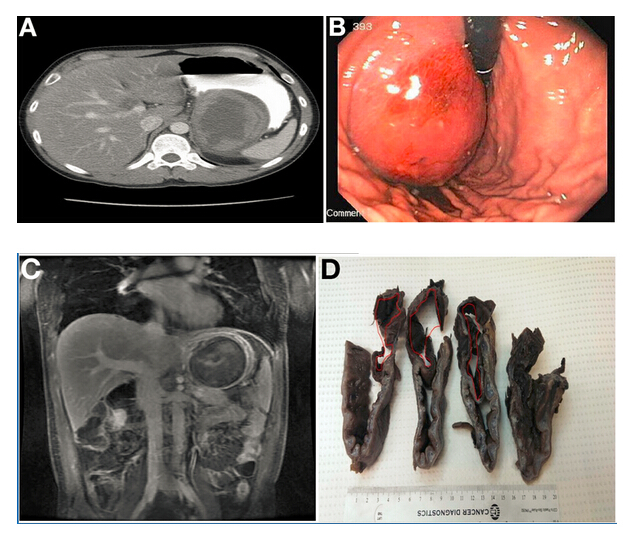

腹部計(jì)算機(jī)斷層掃描(CT)顯示胃底有一9.8×7.4cm不均質(zhì)腫塊(圖A),在隨后的胃鏡檢查中也發(fā)現(xiàn)該腫塊(圖B)。

腹部磁共振成像(MRI)進(jìn)一步明確為界限清楚、不均質(zhì)腫塊,對(duì)比增強(qiáng)(圖C),提高了對(duì)胃腸道間質(zhì)瘤(GIST)的懷疑。計(jì)劃手術(shù)切除。

術(shù)中發(fā)現(xiàn)可疑病變具有定義不明的外科平面和顯著的周?chē)w維化,最終行空腸食管Roux-en-y吻合術(shù)。組織學(xué)檢查(圖D)和顯微鏡標(biāo)本(圖E)顯示正確診斷。

令人驚訝的是,胃大部切除標(biāo)本(圖D)檢查發(fā)現(xiàn)在疑似腫瘤的胃壁區(qū)域內(nèi)有扁平囊。這一扁平囊可以拉伸到9×8×4.5cm。胃囊與真實(shí)胃腔之間有一處共同的壁。通過(guò)此壁的組織學(xué)切片(圖E)顯示了分隔壁兩側(cè)的平滑肌細(xì)胞層和胃黏膜。這排除了GIST,證實(shí)胃重復(fù)畸形的診斷(GDC)。胃重復(fù)畸形是一種罕見(jiàn)的先天性異常,僅占胃腸道所有重復(fù)囊腫的4%至9%。大多數(shù)病例報(bào)告發(fā)生在兒童中且位于胃大彎處。GDC有以下3個(gè)特點(diǎn):(1)囊腫的壁與胃壁相連,(2)囊腫由平滑肌包圍,通過(guò)肌肉與胃壁相連,(3)囊壁排列有胃上皮或其它類(lèi)型的胃黏膜。